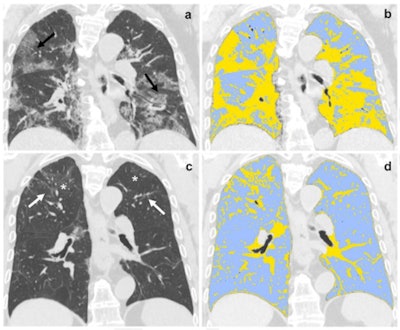

The team conducted a study that included 118 patients who had moderate to severe COVID-19 disease between March and May 2020 (all patients' disease was confirmed by reverse transcription polymerase chain reaction [RT-PCR] testing). All underwent baseline chest CT exams and follow-up exams at six-months; the researchers assessed the exams' qualitative findings, LSS, and QCCT measures, comparing them with baseline CT exam findings. The team assessed three strategies for predicting long-term COVID-19 effects: clinical data alone, radiological data alone, and a combination of the two methods.

At six-month chest CT follow-up, 72% of patients had fibrotic-like changes in their lungs and 42% showed ground-glass opacities. The investigators found that baseline LSS and QCCT scores were effective predictors of fibrotic-like changes at this follow-up exam.